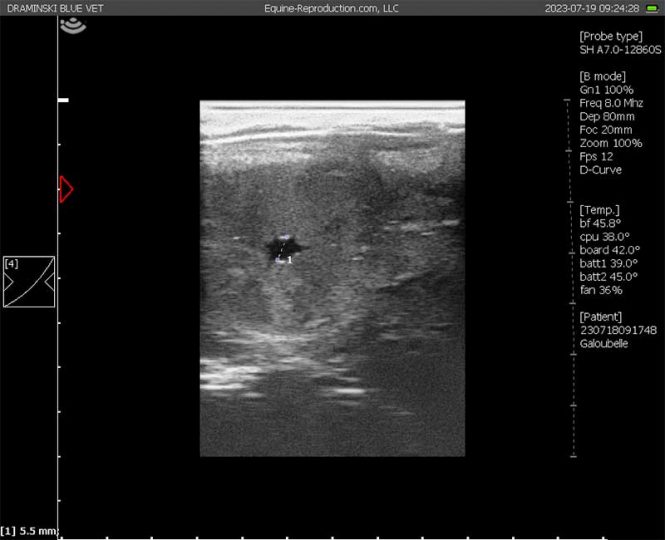

The mare arrived at the Clinic for routine on-site natural mating. She was examined twice daily to determine a suitable opportunity for covering and to determine the time of ovulation. The mare was mated naturally on each occasion by the same Irish Draught stallion. Examinations were then made from Day 12 onwards for pregnancy. The embryonic vesicle when visualised was measured with electronic callipers from two right-angle diameters. Non-pregnancies returned to oestrus spontaneously and pregnancy failures were returned to oestrus by treatment with 125-250 mcg a PGF2a analogue d-cloprostenol. No pharmacological or other treatments were given during any of the pregnancies.

The mare was covered naturally at ten (10) oestrous periods over two breeding seasons by the same stallion. She conceived on seven occasions and returned to oestrus on three. Embryo failure occurred 6 times. On the 10th covering, the pregnancy survived, and a foal born. No medical intervention was used. Pregnancies were found to have failed by 35, 22, 17, 22, 23 and 21 days sequentially. Embryonic vesicles were considered to be crucially small for gestational age on all 6 occasions of failure, with diameters ranging from 2 to 5 mm on Day 14, and from 9 to 14 mm on Days 17/18. Only once did a vesicle grow to more than 18 mm (22 mm). Spontaneous luteal regression with re- turn to oestrus occurred on two occasions resulting in inter-ovulatory intervals of 22 and 23 days. The corpus luteum persisted on the other 4 occasions. Mean diameters of failed embryos on Days 12 to 22 were smaller than normal by 6.44, 9.0, 12.0, 12.8, 13.5, 13.1, 11.6, 10.6, 10.3, 9.8 and 8.0 mm on Days 12 to 22 respectively. This represented the equivalent in mean growth retardation on Days 12 to 22 of > 4, >4, >4, 3.5, 3.5, 4.0, 4.5, 5.5, 6.5, 7.0 and 9 days respectively (Table 1).

On the final and successful cycle, the embryonic vesicle was small- er than the average diameter on Days 12 to 17 and Day 22 by 5.9, 7.8, 8.7, 10.1, 10.5, 10.3 and 3 mm respectively representing a growth retardation of < 3, 2.5, 2.5, 2.5, 3.0, 3.5 and 4.0 days respectively. The embryo proper was not detected on Day 20 and was small when seen on Day 23 (c. 2 mm), representing an estimated retardation in development of 3 days. Its development by Day 30, with the allantoic cavity occupying approximately 25-30% of the conceptus, represented one to two days retardation. Table 1 shows the mean diameters of viable pregnancies in mares examined three times daily for ovulation, and three times daily from 10 days of pregnancy (unpublished data).